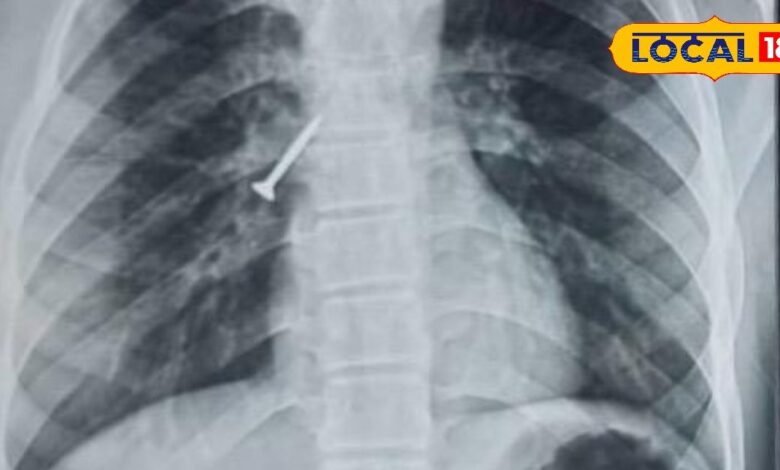

उदयपुर: उदयपुर शहर के बड़ी स्थित टीबी एवं चेस्ट अस्पताल में डॉक्टरों ने एक बेहद जटिल मामले को आसान तरीके से हल कर एक 17 वर्षीय युवक को नया जीवन दिया है. रवींद्रनाथ टैगोर मेडिकल कॉलेज के अधीन संचालित इस अस्पताल में युवक की सांस की नली में फंसे 32 एमएम लंबे लोहे के स्क्रू को बिना किसी ऑपरेशन और बिना बेहोश किए सफलतापूर्वक बाहर निकाल लिया गया. जानकारी के अनुसार युवक सुथारी का काम कर रहा था, इसी दौरान गलती से उसने स्क्रू निगल लिया. यह स्क्रू सीधे उसके दाएं फेफड़े की श्वास नली में जाकर फंस गया.इसके बाद युवक को लगातार खांसी, छाती में तेज दर्द और बलगम में खून आने जैसी गंभीर परेशानी होने लगी.परिजन तुरंत उसे अस्पताल लेकर पहुंचे, जहा उसे भर्ती किया गया.डॉक्टरों ने जांच के बाद स्थिति को गंभीर मानते हुए अगले ही दिन इस प्रक्रिया को करने का फैसला लिया.

आमतौर पर ऐसे मामलों में मरीज को बेहोश कर सर्जरी या रिजिड ब्रोंकोस्कोपी की जरूरत पड़ती है, लेकिन यहां डॉक्टरों ने फ्लेक्सिबल ब्रोंकोस्कोपी तकनीक का इस्तेमाल किया.इस तकनीक की मदद से बिना चीर-फाड़ और बिना एनेस्थीसिया के स्क्रू को बाहर निकाल लिया गया.